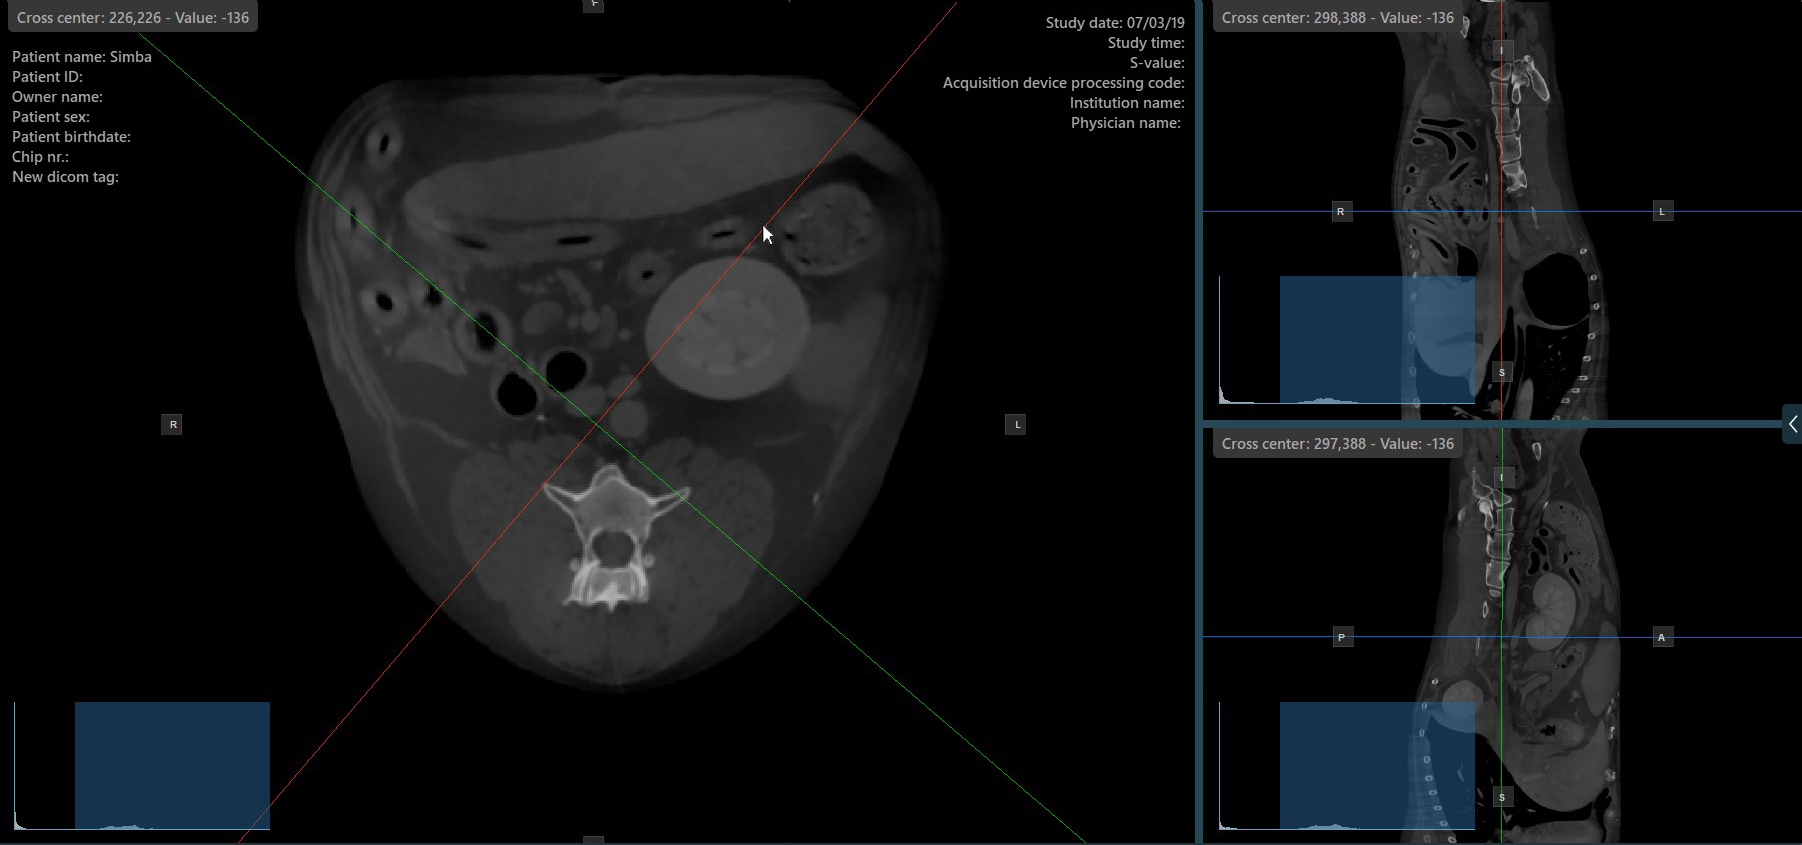

Altering the rotation of a slicer will change the orientation of the corresponding image planes. Individual slicers can be selected by using the Select Item (Default) tool, assigned to the right mouse button by default.

Once the specific slicer is selected, drag the slicer in the desired direction to rotate it. The corresponding image plane’s orientation changes accordingly.